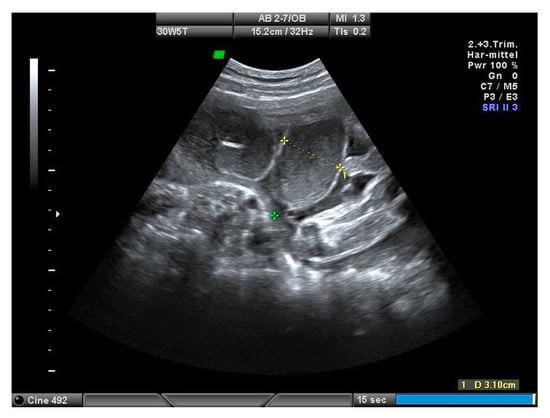

Prenatal Prediction of Outcome by Fetal Gastroschisis in a Tertiary Referral Center

2. Materials and Methods